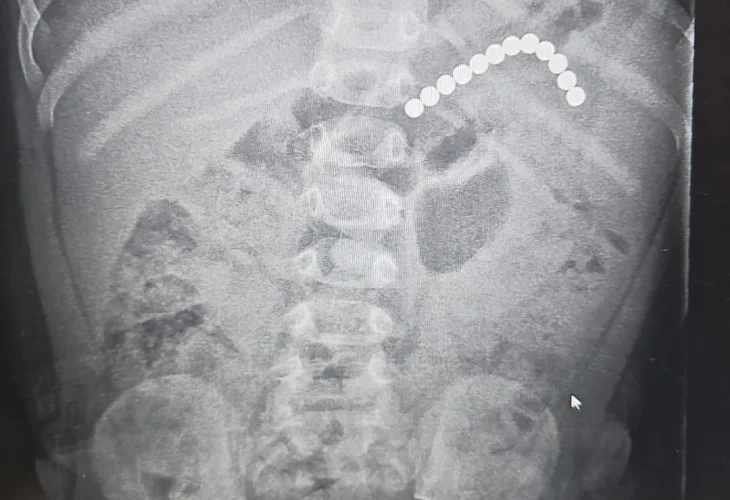

צילום מקיבתו של הפעוט (צילום: דוברות בית החולים אסותא, אשדוד)פעוט בן שנה ושלושה חודשים הובהל בשבוע שעבר למיון ילדים בבית החולים הציבורי אסותא אשדוד, לאחר שבלע מגנטים קטנים מתוך משחק של אחיו הגדול. בצילום שנעשה התברר כי 12 מגנטים עגולים נלכדו במערכת העיכול שלו, מחוברים זה לזה בצורת שרשרת. הילד הגיע לבית החולים כשהוא סובל מתיאבון ירוד, ובבדיקות חוזרות נמצא כי המגנטים לא זזו ממקומם - מצב מסוכן במיוחד.

צוות המיון קיבל החלטה על גסטרוסקופיה דחופה. במהלך הפעולה, שבוצעה בידי ד"ר חני טאף, מנהלת גסטרואנטרולוגיה ילדים, ובסיוע ד"ר איתן דמארי, סגן מנהל מחלקת הילדים ומומחה בתחום, הצליחו הרופאים להוציא עשרה מגנטים מתוך הקיבה. אחד מהם נמצא כבר שקוע ברירית הקיבה. שני מגנטים נוספים שהיו במעי הדק נפלטו בהמשך באופן טבעי, ללא סיבוכים.